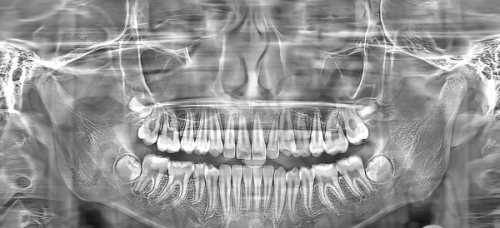

此外,医院还配备了精良的口腔综合治疗台、口腔X光机等设备。口腔综合治疗台具有多种功能,可以满足不同口腔治疗的需求。口腔X光机可以为医生提供清晰的口腔影像,帮助医生更好地诊断口腔疾病。这些设备的使用,不仅提高了医院的诊疗水平,也为患者提供了更加优质、效率高的口腔诊疗服务。